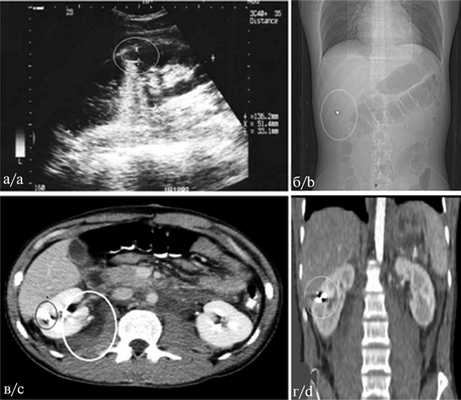

Пациент З., 23 лет, поступил в операционное отделение без предварительного обследования в приемном отделении 27.07.12 в 16:30, через 1 ч после ранения, полученного на улице. Состояние тяжелое, в сознании, вынужденное положение на правом боку. Предъявлял жалобы на боли в животе, общую слабость, головокружение. АД 110/70 мм рт.ст., ЧСС 120 в минуту, ШИА 1,09. На боковой стенке живота слева по передней подмышечной линии под реберной дугой рана размером 0,3×0,3 см, без эмфиземы, с незначительным кровотечением. Живот вздут, болезненный во всех отделах, положительные симптомы раздражения брюшины. При рентгенографии груди и живота легочные поля прозрачны, газ, жидкость не определяются. Контуры аорты четкие. В проекции правого подреберья определяется инородное тело — пуля от пневматического оружия. При УЗИ, выполненном на операционном столе, в брюшной полости выявлена свободная жидкость во всех отделах, в полости малого таза — до 5 см. Почки подвижны, топография их обычная. Правая почка размером 12,1×5,2 см, левая размером 10,8×4,8 см. Паренхима шириной 1,9×2 см средней эхогенности с гипоэхогенными пирамидками. Чашечно-лоханочная система не расширена, справа удвоена. С обеих сторон определялись эхосигналы расцененные как конкременты размером от 0,2 до 0,8 см (рис. 2, а). Рис. 2. Слепое пулевое ранение живота из пневматического оружия у пациента З. а — УЗИ, линейный эхосигнал (обведен) в правой почке, б, в, г — СК-томограмма. а — расширительная пуля в проекции правого подреберья (обведена); в — аксиальный срез, инородное тело (обведено черным), паранефральная гематома и экстравазация контрастного вещества (обведено белым); г — фронтальная реконструкция, инородное тело в правой почке (обведено). Забрюшинная клетчатка неоднородная из-за кровоизлияния.

При экстренной лапаротомии выявлена большая срединная забрюшинная гематома. На передней стенке нисходящей ободочной кишки непроникающая сквозная рана, раневой канал которой проходит в мышечном слое. В начальном отделе тощей кишки на расстоянии от 5 до 25 см от связки Трейца выявлены 4 раны диаметром от 0,3 до 0,5 см, проникающие в просвет кишки. На задней париетальной брюшине в центре забрюшинной гематомы дефект с умеренным кровотечением. Аорта временно пережата под диафрагмой. Вскрыта забрюшинная гематома. На передней стенке аорты на 2 см ниже поджелудочной железы выявлена рана (входная) диаметром 0,3 см, проникавшая в просвет аорты. На правой заднебоковой стенке аорты вторая рана (выходная) диаметром 0,6 см. Раны аорты ушиты полипропиленовой нитью 5/0. Ушиты раны тощей и ободочной кишки. Выявить пулю в брюшной полости не представилось возможным. Выполнены назоинтестинальная интубация, санация и дренирование брюшной полости. Общая кровопотеря составила 3000 мл. Вся кровь собрана аппаратом Cell Saver, реинфузия 800 мл взвеси эритроцитов с гематокритом 75%. Проведена интенсивная заместительная и антибактериальная терапия. Дренажи из брюшной полости удалены на 4—5-е сутки. На 6-е сутки после операции выполнена СКТ брюшной полости с внутривенным контрастным усилением. На СК-томограмме в правом подреберье четко определялась тень недеформированной расширительной пули от пневматического оружия (см. рис. 2, б). На аксиальных срезах (см. рис. 2, в) и в правой почке выявлено инородное тело, а также паранефральная гематома справа объемом 70 см 3 , с затеканием контрастного вещества за контур почки через раневой канал в ней. При фронтальной реконструкции в правой почке четко определяется инородное тело высокой плотности (см. рис. 2, г). Клинически ранение правой почки никак себя не проявляло. При динамическом УЗИ паранефральное кровоизлияние регрессировало. Пациент выписан на 24-е сутки после операции в удовлетворительном состоянии. Повторно был осмотрен через 6 мес, жалоб не предъявлял. С учетом отсутствия признаков повреждения чашечно-лоханочного аппарата, незначительных размеров инородного тела выбрана консервативная тактика.